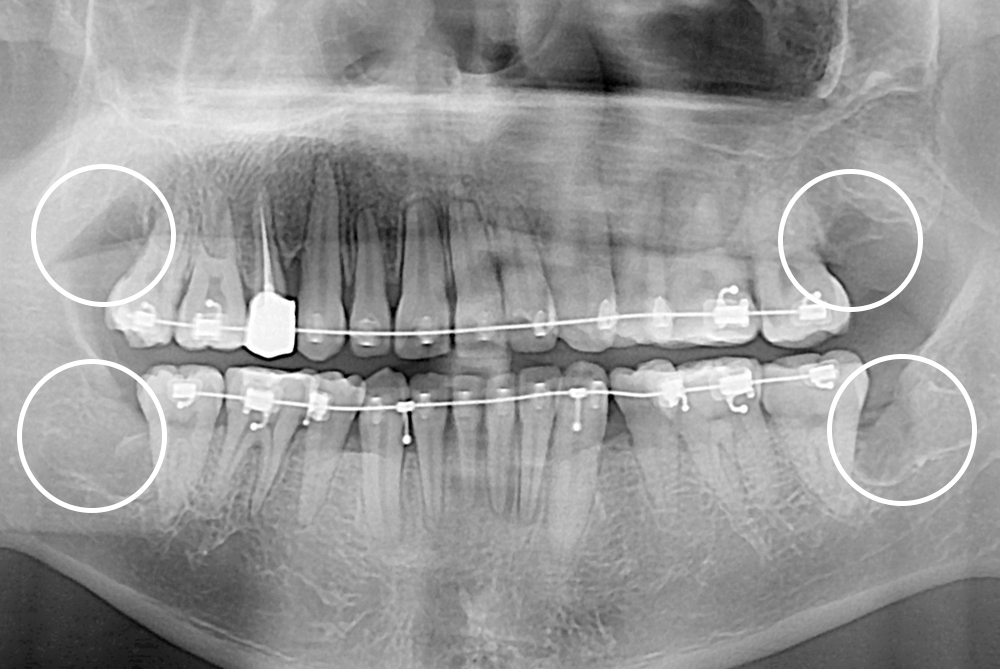

[사랑니] 매복 사랑니 발치

치료전 : 2019-07-12